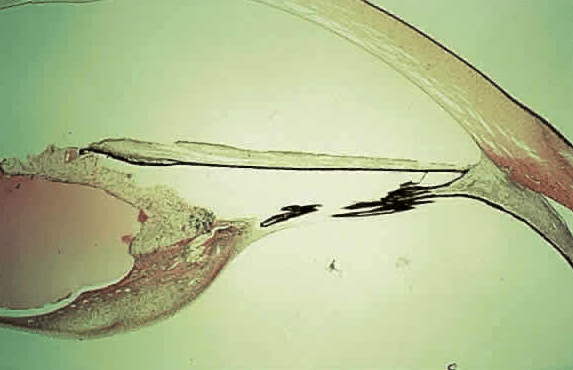

В настоящей работе представлен клинический случай ранее не выявленной ПГА у пациентки А. 69 лет. Пациентка обратилась в ФГБНУ «НИИГБ» с жалобами на снижение зрения. Левый глаз (OS) видит хуже правого глаза (OD) с детства. Более ранние визиты пациентки к офтальмологам ограничивались только подбором очков. При рефрактометрии выявлено наличие в OD простого гиперметропического астигматизма ст. 1,0d., в OS — смешанного астигматизма ст. 2,5d с превалированием миопического компонента. Максимальная острота зрения с коррекцией правого глаза равнялась 0,7, левого — 0,2. Проведение биомикроскопии выявило признаки незрелой катаракты в виде умеренных помутнений в ядре и кортикальных слоях хрусталика обоих глаз. Изменения в хрусталике OS не ограничивались возрастной катарактой. Так, на ЗКХ в парацентральной зоне и несколько назальнее отчетливо определялась так называемая точка Миттенфорда — участок фиброзных изменений с кальцификатами, от которого в СТ отходит тонкий тяж — КК, идущий по направлению к заднему отрезку глаза (рис. 1). Обнаружены фиброзные помутнения на поверхности ЗКХ диаметром до 2—2,5 мм. Их интенсивность в центре значительная, по периферии — менее выраженная, в виде полупрозрачного ободка. Определялось, но неотчетливо, сосудистое русло фетальной артерии, распространяющееся по задней поверхности хрусталика в виде отдельных веточек с красноватым оттенком (рис. 2). Последнее с большой долей вероятности указывало на наличие остаточного кровотока в русле ПГА. Результаты офтальмоскопии подтвердили S-образную, несколько вытянутую форму (рис. 3) и классический тип прикрепления КК к ДЗН (с назальной стороны). Кроме этого, отмечено Y-образное расширение КК в зонах его контакта с ЗКХ и ДЗН.

Рис. 1. Биомикроскопическая картина в области прикрепления Клокетова канала к задней капсуле хрусталика.